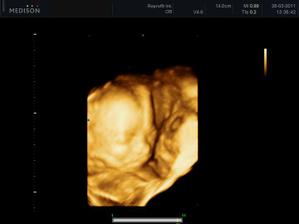

28.1.2011 - Tak máme za sebou velký utz a podle pana doktora je vše v pořádku, ještě musíme počkat na výsledky krve - snad dopadnou dobře. Prcek byl nádhernej, odpovídáme 12+1 a měříme 6,17cm. Nejdříve s náma mimíšek nechtěl moc spolupracovat, stavěl se dokonce i na hlavičku, prostě všelijak, jen né tak, jak by pan doktor potřeboval, tak jsem musela jít na 15 minut pochodovat na hodbu, aby se nám mňous přemístil. Pak se nám ještě chvilku schovával a zakrýval si pusinku ručičkou, ale nakonec se ukázkově natočil a pózoval. Byl to krásný zážitek.